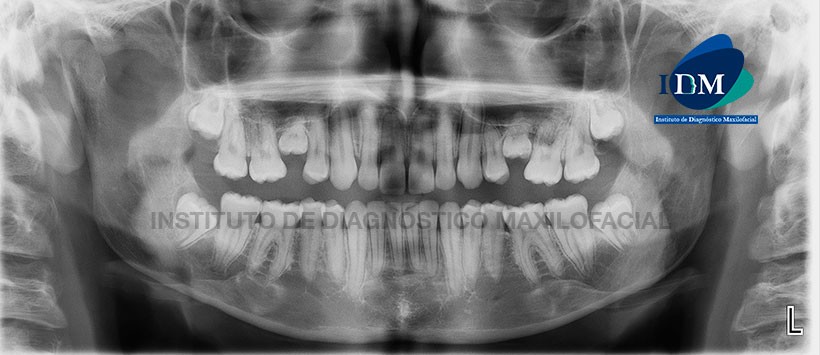

En evaluación de la radiografía panorámica (Figura 1) se aprecia piezas 5.5 y 6.5 en infraoclusión, no se evidencian los gérmenes dentarios para las piezas 1.5 y 2.5.